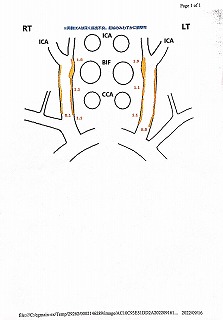

090 脳ドック

2024.18.14 荒尾市民病院 2023.08.10 荒尾市民病院

2024 PDF 2023 PDF

22.9.16 荒尾市民病院

2014(H26)7.29 岡山淳風会